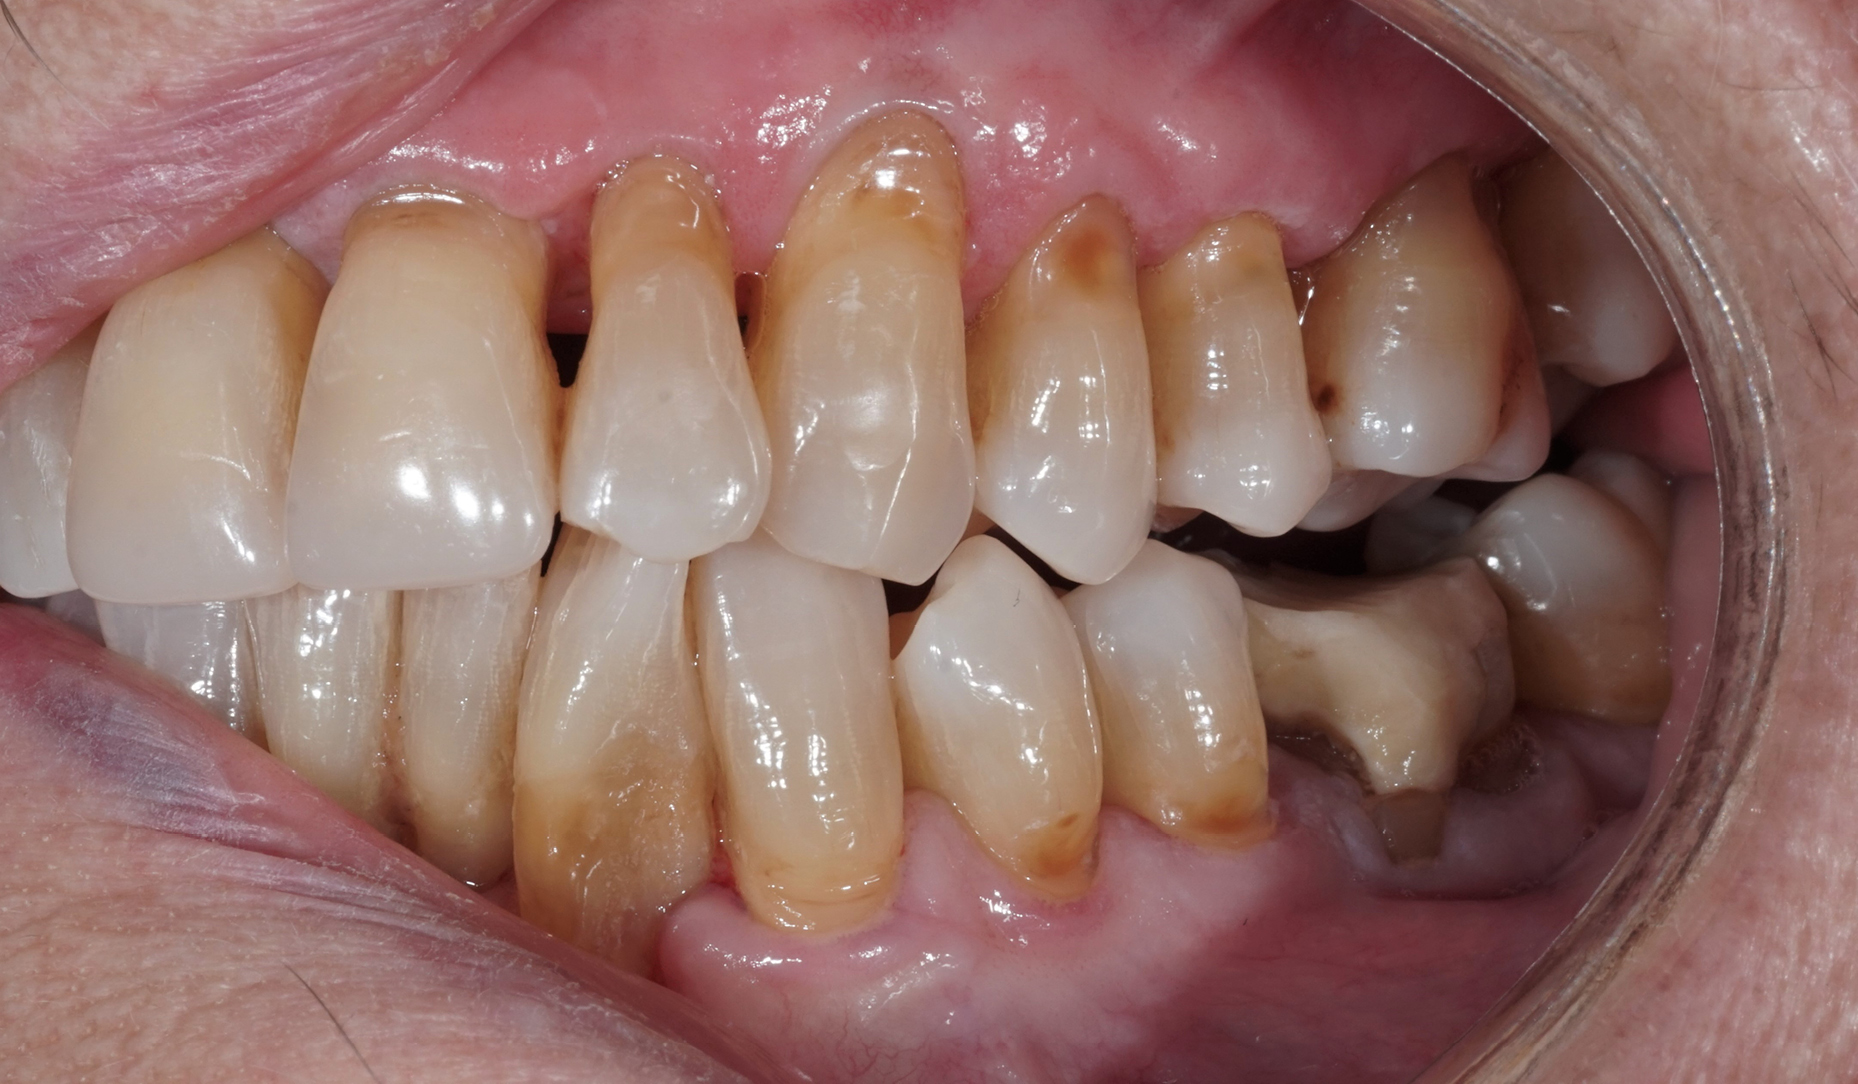

Ryc. 2. Stan kliniczny podczas pierwszej wizyty wgabinecie stomatologicznym.

Ryc. 3. Zgryz otwarty w lewym, tylnym obszarze żuchwy.